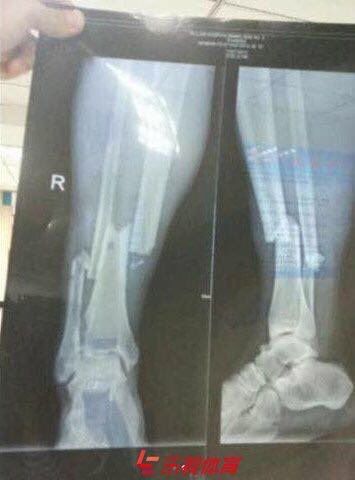

Penampakan Hasil Ronsen

Setelah kejadian tersebut foto ronsen kaki Demba Ba pun tersebar di media sosial.

Dilansir dari 101greatgoals, jika dilihat dari foto tersebut cukup untuk mengatakan bahwa keadaan kaki Ba tidak terlihat baik untuk masa depannya.